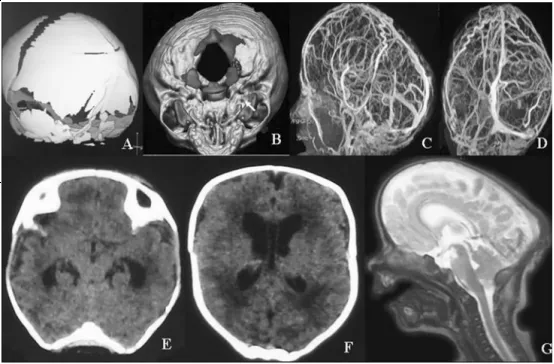

INC国际儿童脑瘤大咖、世界小儿神经系统知名杂志《Childs Nervous System》现任主编Concezio Di Rocco教授发表研究《Complex craniosynostoses:a review of the prominent clinical features and the related management strategies》(...